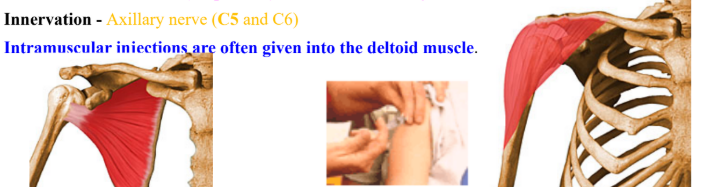

Deltoid | Acromion process, anterior border of lateral 1/3 clavicle, lower lip of crest of spine | Deltoid tuberosity | Anterior flexes and medially rotates Middle abducts Posterior extends and laterally rotates | Axillary nerve |